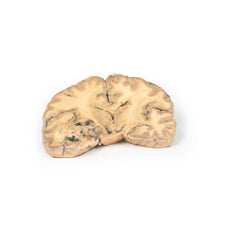

3D Printed Glioma Grade 3-4, Causing Papilloedema

The specimen shows a large intracerebral lesion, which has obliterated the lateral ventricles and

the inner 2/3 of the internal capsule and basal ganglia on the right side. It is infiltrating across the corpus

callosum and distorting the aqueduct. The tumour is fairly well demarcated and vascular with numerous areas of

haemorrhage and necrosis, causing its mottled variegated appearance.